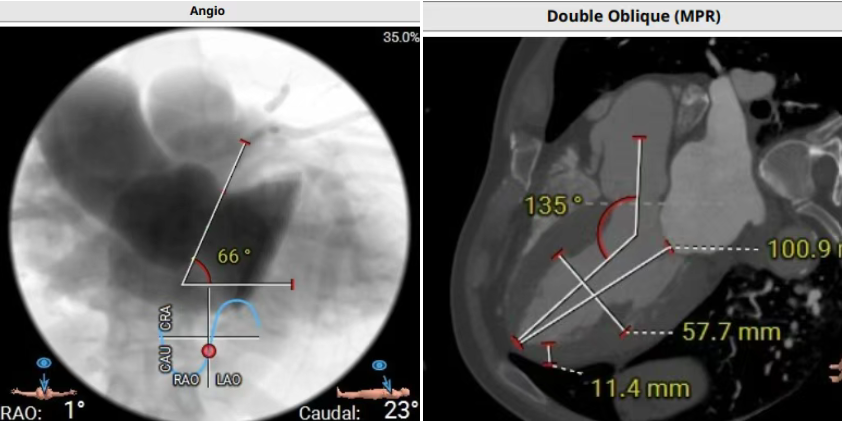

术前CT评估提示,患者主动脉瓣三叶瓣,瓣叶增厚,舒张期右冠瓣脱垂,右冠瓣瓣叶轻度钙化,存在三个瓣窦,分布较均匀;主动脉瓣环周长折算直径28.0mm;左心室流出道周长折算直径29.5mm,无钙化,无狭窄;STJ直径35.3mm,升主动脉直径41.8mm;双侧冠脉开口高度可LCA13.5mm ,瓣叶长17.2mm;RCA33.9mm,瓣叶长10.0mm;侧左冠脉轻度钙化;横位心,左室主动脉夹角为135°;